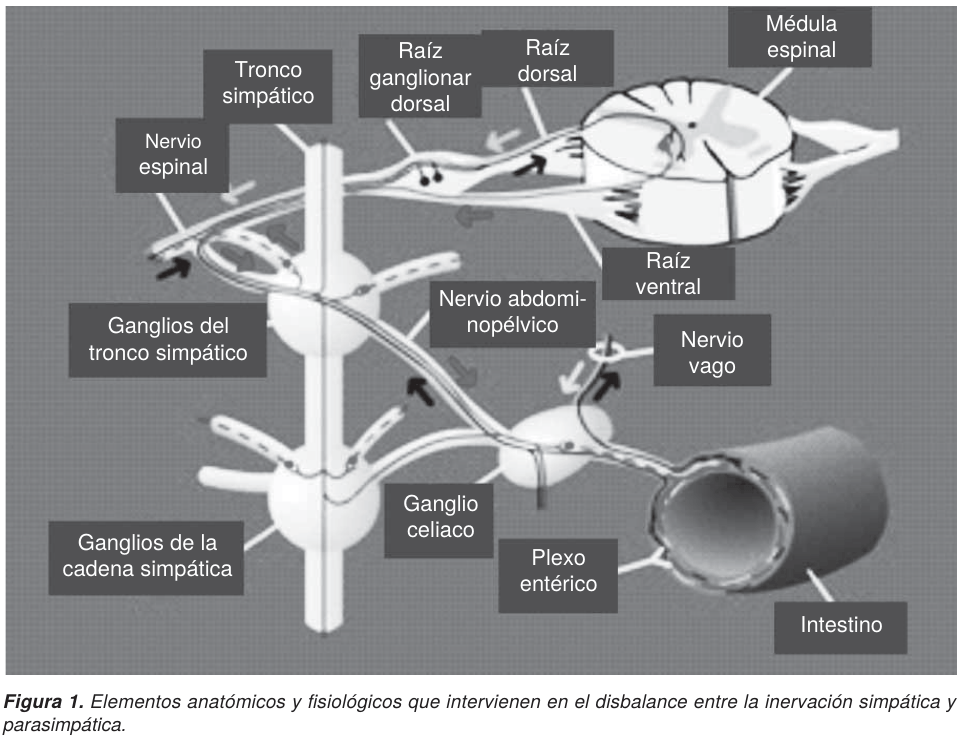

Aunque el SO no tenga una etiología bien sustentada, y otros autores la consideren como desconocida,21 se presume un disbalance entre la inervación simpática y parasimpática del colon, su dilatación es producida por factores no mecánicos. Este concepto de que la pared del colon y recto puede relajarse en respuesta a estímulos fisiológicos y farmacológicos, propuesto por el mismo Ogilvie, explica un desequilibrio autonómico del control intrínseco como base del síndrome. Esta hipótesis se ha comprobado al obtener un alivio sintomático por medio de un bloqueo adrenérgico conseguido por la estimulación colinérgica o por el uso de neostigmina sola (Figura 1).